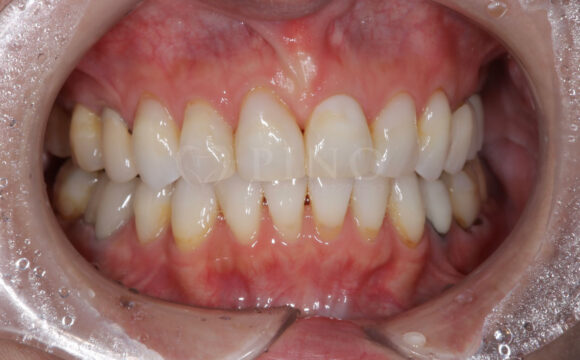

症例2:ワイヤー矯正後の後戻りが気になる(50代女性)

主訴 ワイヤー矯正後に後戻りが気になる 診断名 叢生 治療方法 マウスピース部分矯正 抜歯 なし オルソパルス なし 治療期間 10ヶ月 費用 436,000円+補綴費用360,000円 副作用・注意点 矯正後の後戻りを防ぐためリテーナーの使用が必要となる 備考 1年4ヶ月で補綴も完了した -